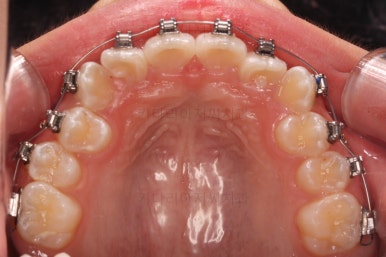

초진 시 입안의 모습입니다.

앞니가 안으로 굽어 들어간 양상인데요. 흔히 "옥니"라고 표현합니다.(뻐드렁니의 반대개념)

전반적으로 치열이 삐뚤삐뚤하고요.

오른쪽 상단 사진을 보시면 어금니의 높이와 앞니의 높이가 차이가 많이 납니다.

앞니가 솟구쳐 있는 양상인데요.

그 이유 때문에 어금니로 다물었을 때의 위아래 앞니가 많이 겹쳐서 아래 앞니가 아예 보이지 않는 상황이었어요.

이를 "과개교합"이라고 표현합니다.

그리고 전반적으로 아래 치열이 윗니에 비해 뒤로 밀려 있어서, 어금니의 맞물림이 좋지 못하고 듬성듬성해 보이는 상황이었어요.